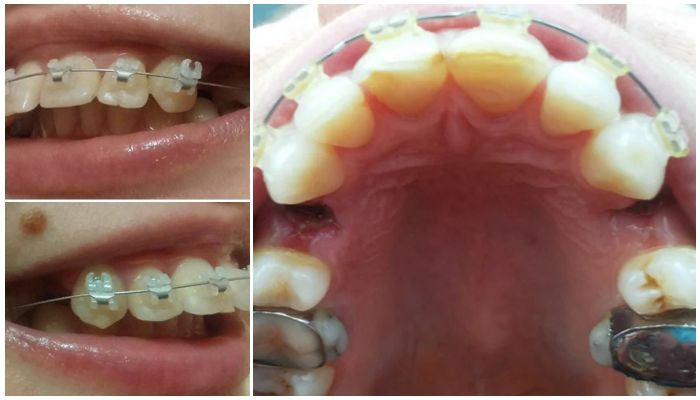

Удалять четверки необходимо подросткам и взрослым пациентам, у которым скученность зубов вызвана анатомическими особенностями челюсти. При узкой кости и больших молярах происходит сдвиг клыков и резцов. В результате отдельные элементы искривляются, наслаиваются друг на друга и выбиваются из ровного ряда. Если вернуть на место выпирающие части невозможно, с удалением тянуть не стоит. Определить необходимость данного вмешательства можно по снимку, который выполняется для всех пациентов до и после установки корректирующей системы.

Большинство пациентов перед установкой корректирующих систем рассматривают фото зубов в брекетах.

На одних иллюстрациях видно, что было проведено предварительное удаление отдельных элементов, а на других ряд остается целым. У пациентов напрашивается вопрос о том, можно ли поставить брекеты без предварительной экстракции. Ответить на него однозначно стоматологи не могут. Многое зависит от того, какой размер имеет челюсть и как в ней располагаются элементы.